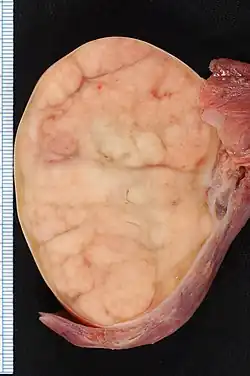

7.4 × 5.5-cm seminoma in a radical orchiectomy specimen. | |